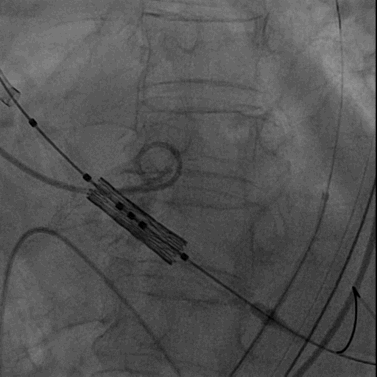

22mm球囊预扩张

置入纽脉医疗29mm球囊扩张式PrizValve